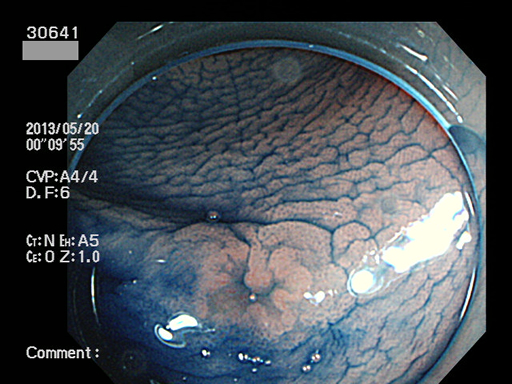

上記100名より抽出した平坦・陥凹型腺腫(=癌化の危険が高いが見落としやすい病変)の内視鏡写真

30640 30641 30643 30644 30645 30646 30647 30648 30649 30650 30653 30654